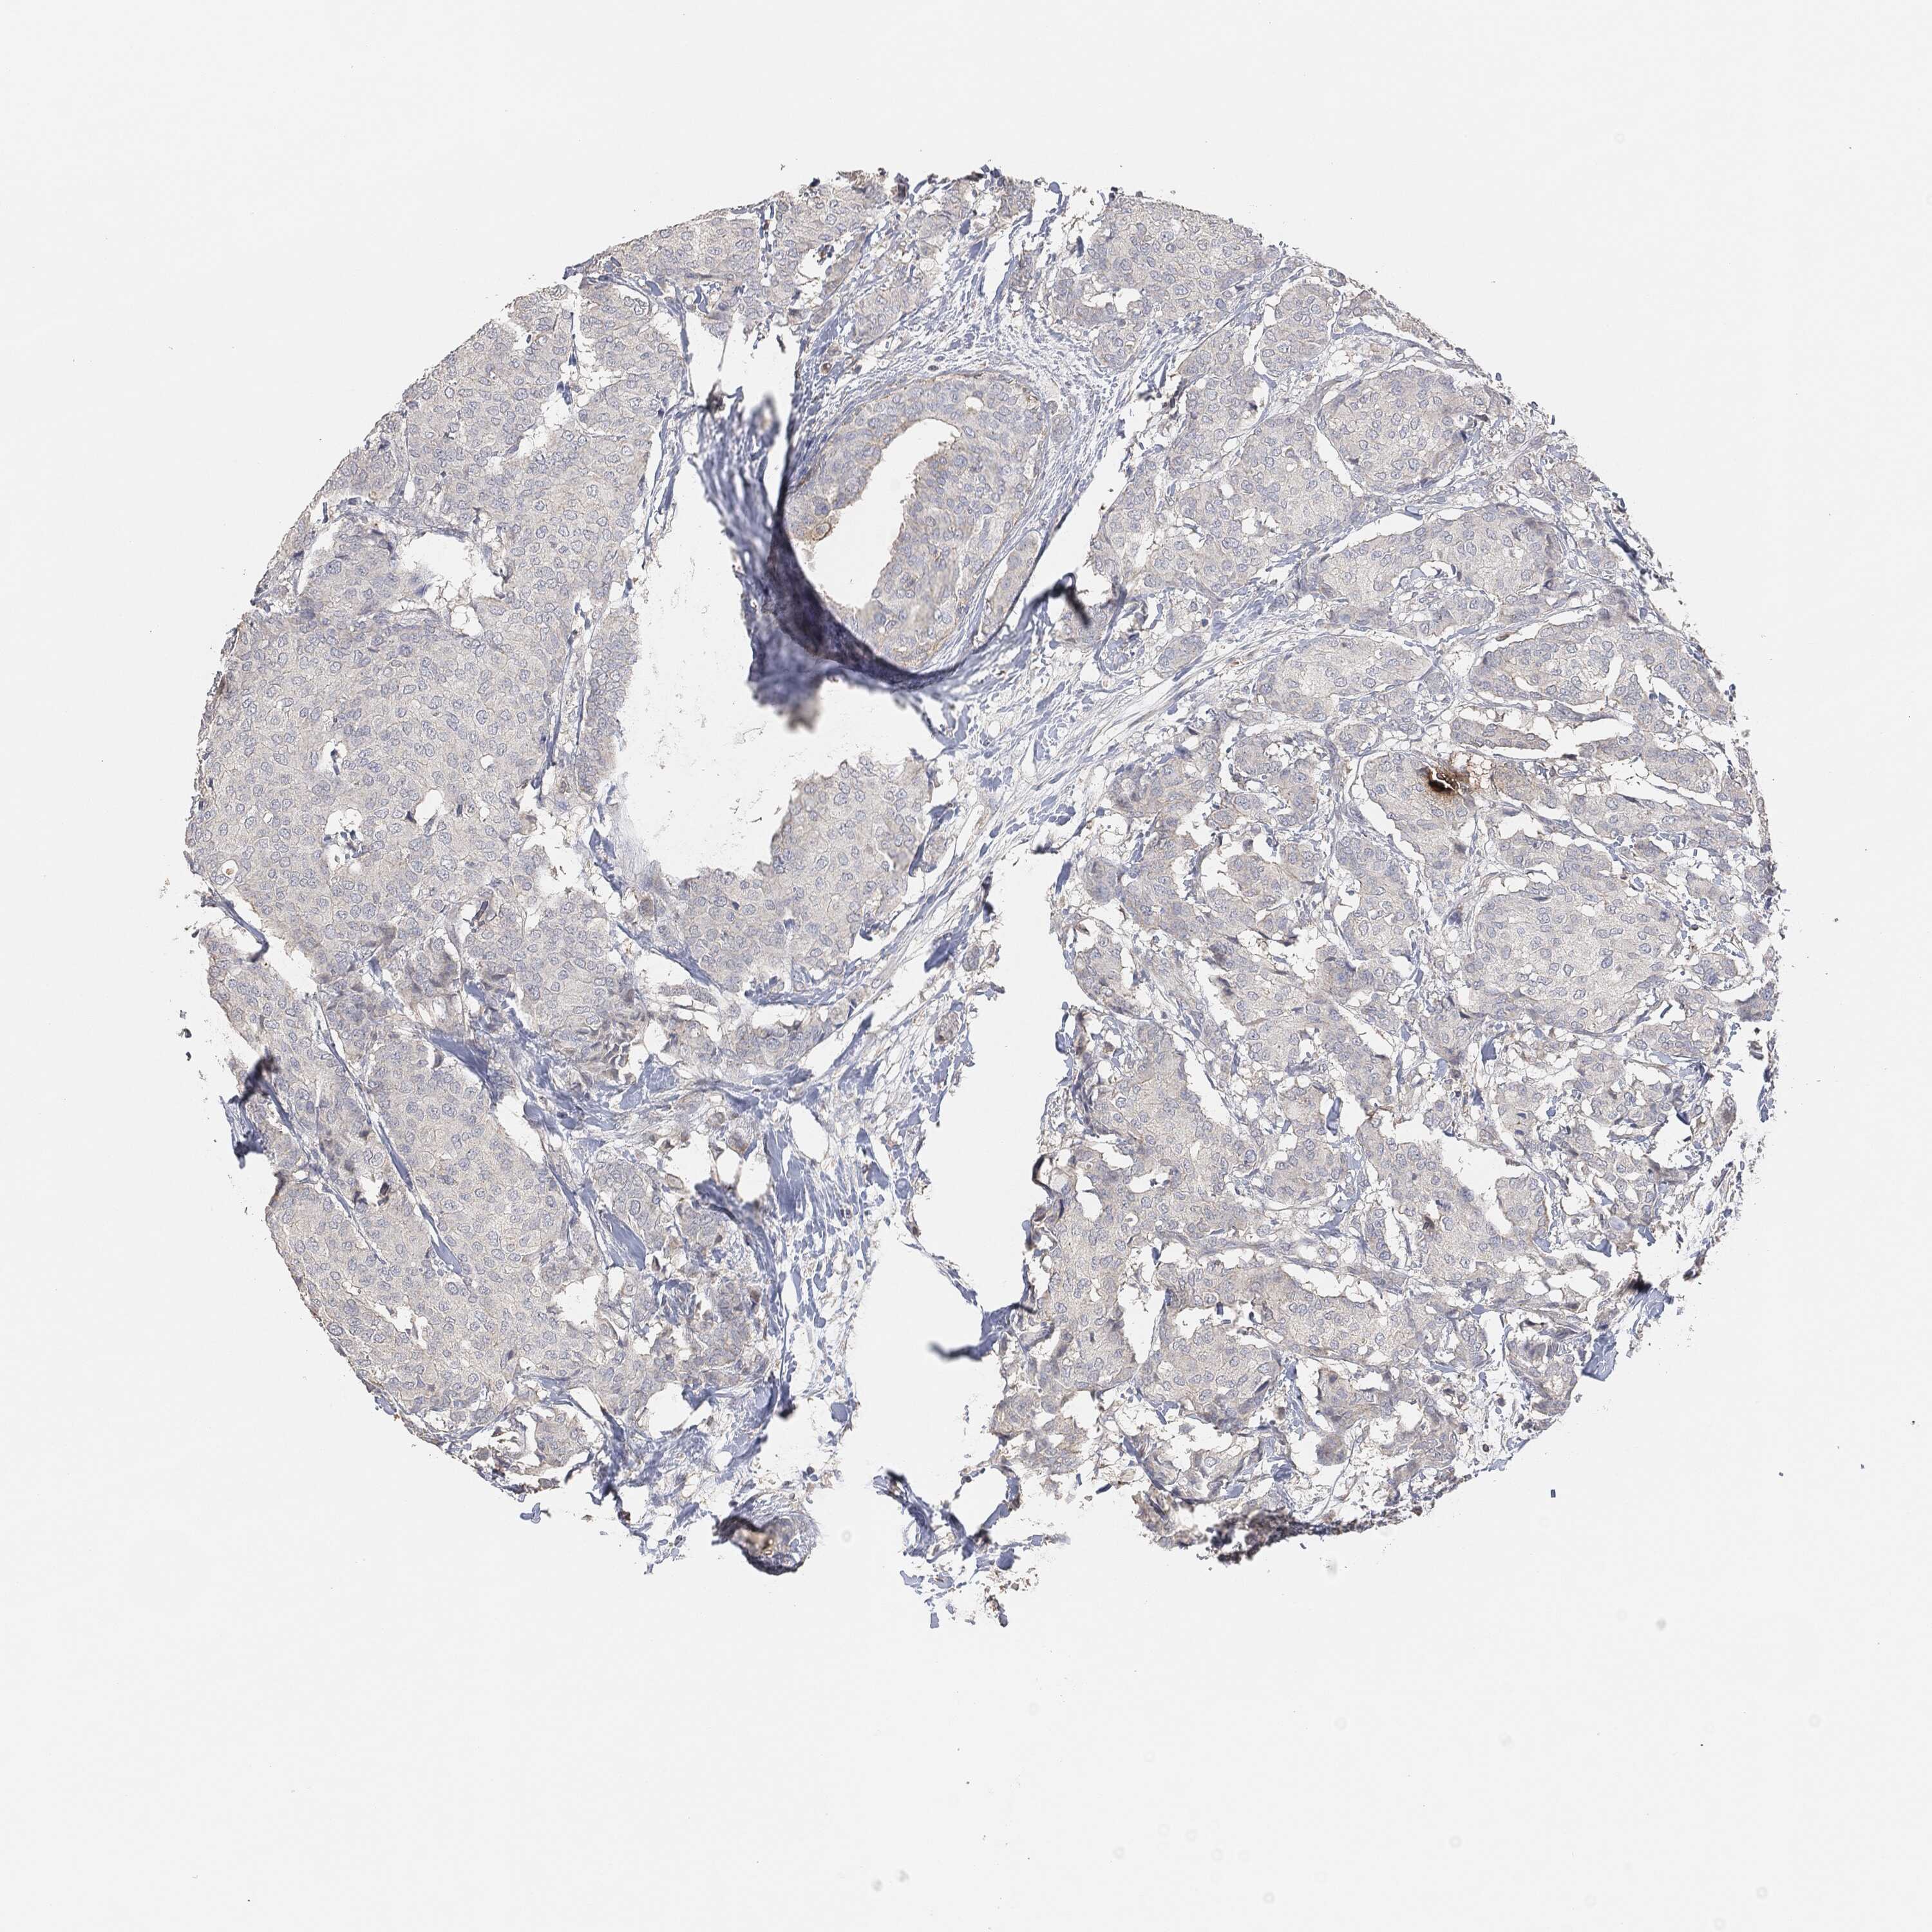

BRCA TCGA BRCA VALIDATION PROTEIN EXPRESSION

ANTIBODIES

AND

VALIDATION